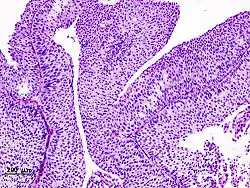

Squamous cell carcinoma of cervix | Invasive Squamous Carcinoma of the Cervix. Cold Knife Cone. | Category: Histopathology of squamous cell carcinoma of the cervix | Invasive squamous carcinoma of cervix |

![]() |